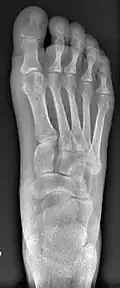

Before_syndesmosis_surgery

Fig. 4a: Before surgery

2_years_after_syndesmosis_surgery

Fig. 4b: 2 years after surgery

Syndesmosis procedure addresses specifically the two fundamental problems of metatarsus primus varus deformity that gives rise to the bunion deformity. They are leaning and instability of the first metatarsal bone . Syndesmosis procedure uprights the leaning first metatarsal bone with strong binding sutures between it and the second metatarsal bone (Fig. 2) and then also stabilizes it uniquely by creating a fibrous connecting bridge between these two bones (Fig. 3, 4). First metatarsal bone can be readily realigned because by definition of the metatarsus primus varus deformity its first metatarsal is abnormally loose and mobile.